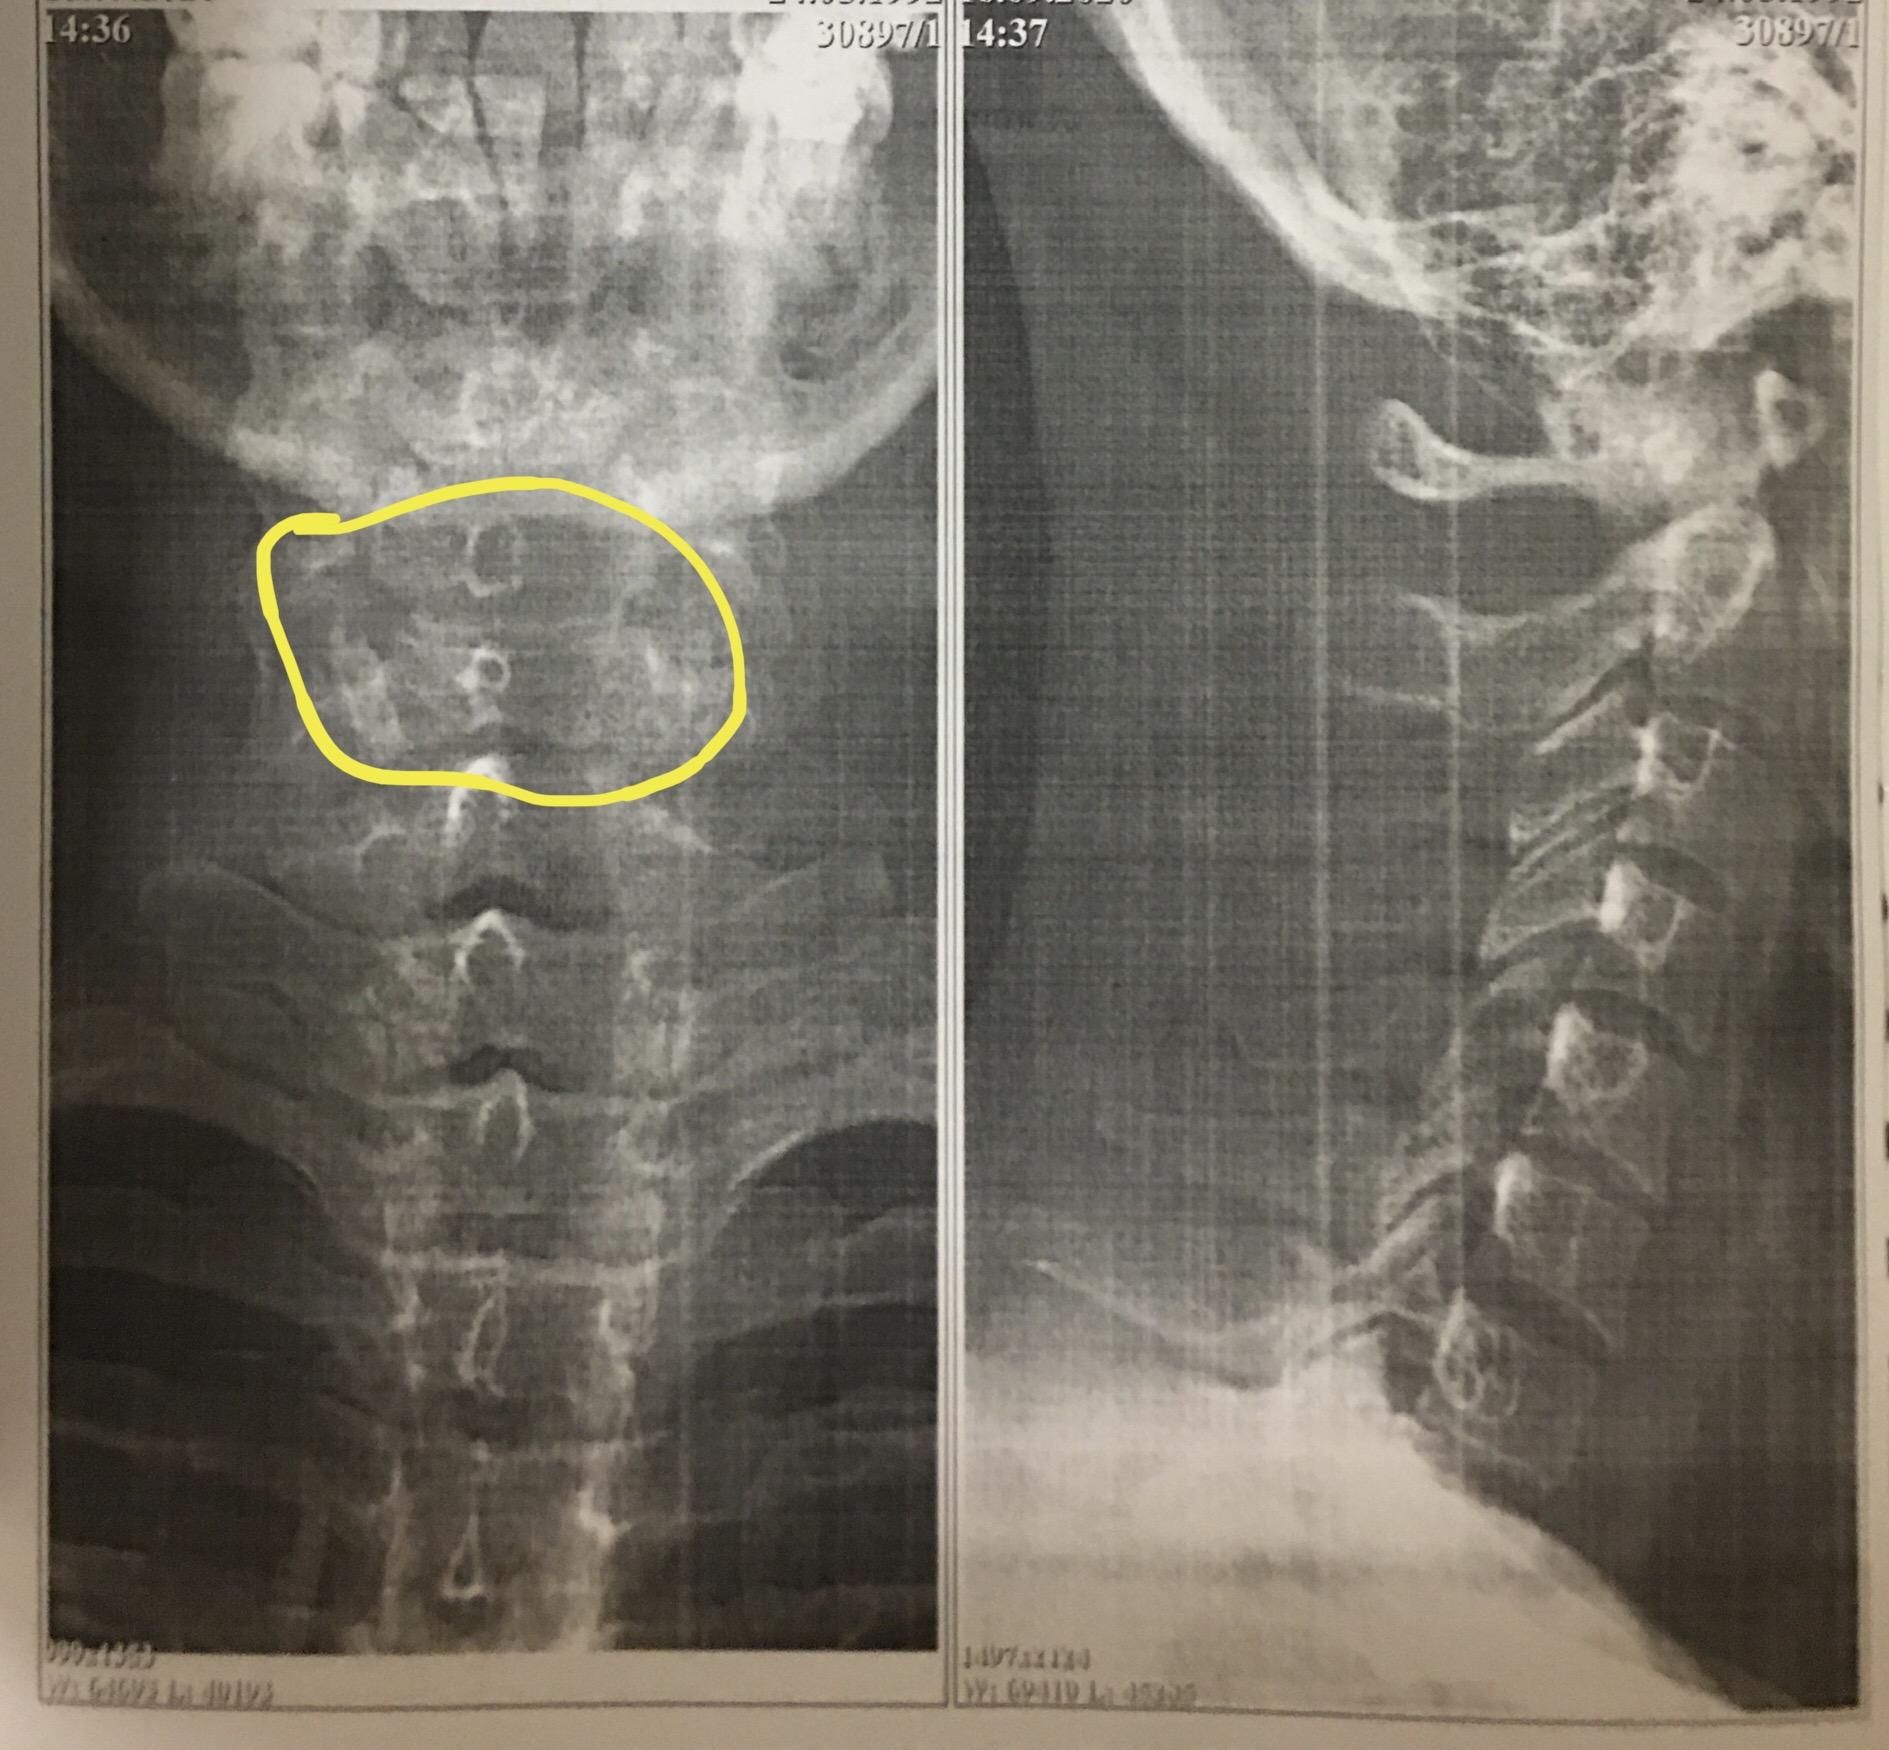

Рентгеновские снимки крестцово-копчикового отдела позвоночника